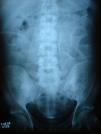

AssessmentThe Kt/V peritoneal was low and peritoneal equilibration test was of a high transporter. At admittance, the physical examination revealed diffuse abdominal pain without peritoneal irritation signs. The effluent had three white bloodcells/mm3, and cultures of dialysate showed no growth of bacteria or fungi. He had anemia and CD4 count was above 400mm–3. An abdominal radiograph showed marked peritoneal fibrosis outlining bowel loops (Fig. 1). A computed tomographic scan of the abdomen confirmed thickening of the peritoneum without intestinal obstruction (Fig. 2).